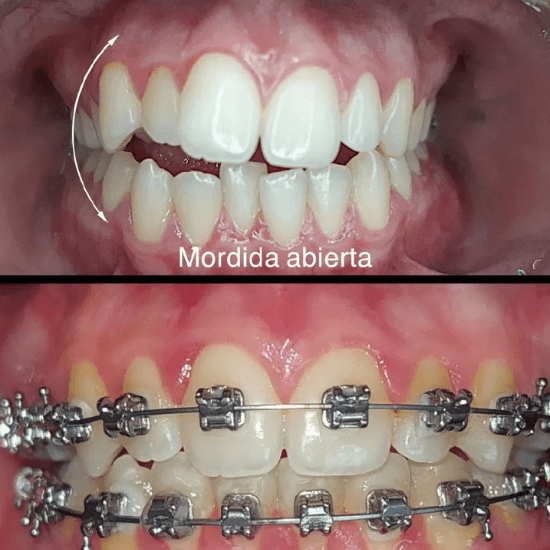

Resultados reales, sonrisas auténticas

– Mordida irregular, como sobremordida, submordida o mordida cruzada.